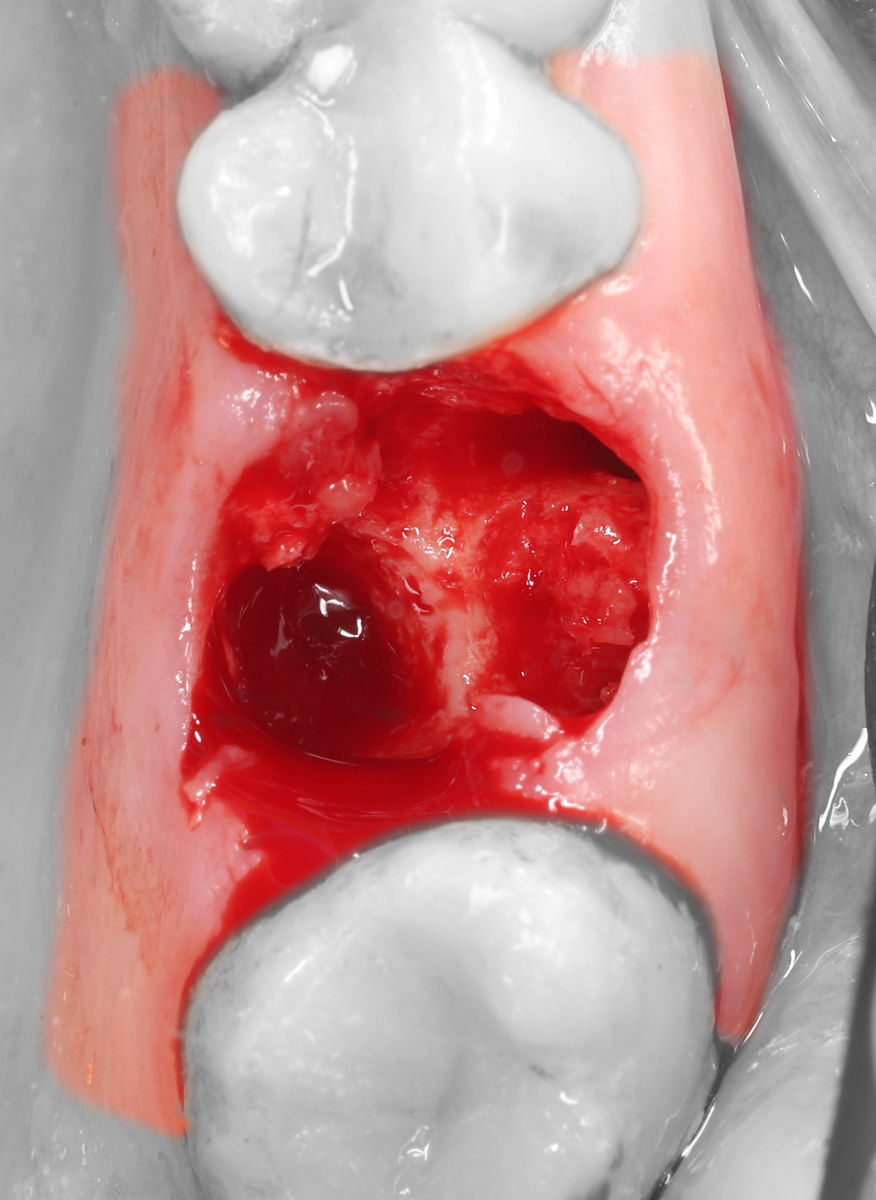

Классическая одномоментная имплантация 2.6 + крестальный синус-лифтинг

3) Остеотомия имплантантного проведена с помощью имплантантных фрез и остеотомов.